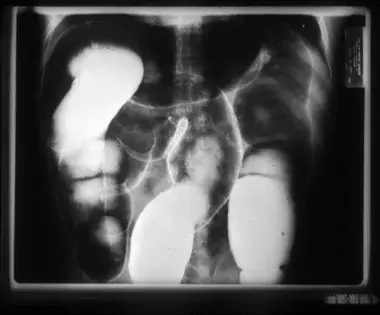

Salient features on gross examination of the colon or esophagus in patients with chronic chagasic gastrointestinal disease (megadisease) include dilatation and muscular hypertrophy of the affected organs (see images below). [57, 58, 59] Focal inflammatory lesions with lymphocytic infiltration are visible on microscopy. The number of neurons in the myenteric plexus often is markedly reduced, and periganglion and intraganglion fibrosis with accompanying Schwann cell proliferation, along with lymphocytosis, are present in most patients with megadisease. The functional effects of this parasympathetic denervation generally are limited to the esophagus or colon, although clinically manifest dysfunction of the ureters, biliary tree, and other hollow viscera has been reported. [60]

Barium swallow radiographic study of a Brazilian patient with chronic Trypanosoma cruzi infection and megaesophagus. The markedly increased diameter of the esophagus and its failure to empty are typical findings in patients with megaesophagus caused by Chagas disease. Courtesy of Dr. Franklin A. Neva, Bethesda, MD.

Air-contrast barium enema of a Bolivian patient with chronic Chagas disease and megacolon. The markedly increased diameters of the ascending, transverse, and sigmoid segments of the colon are readily apparent.